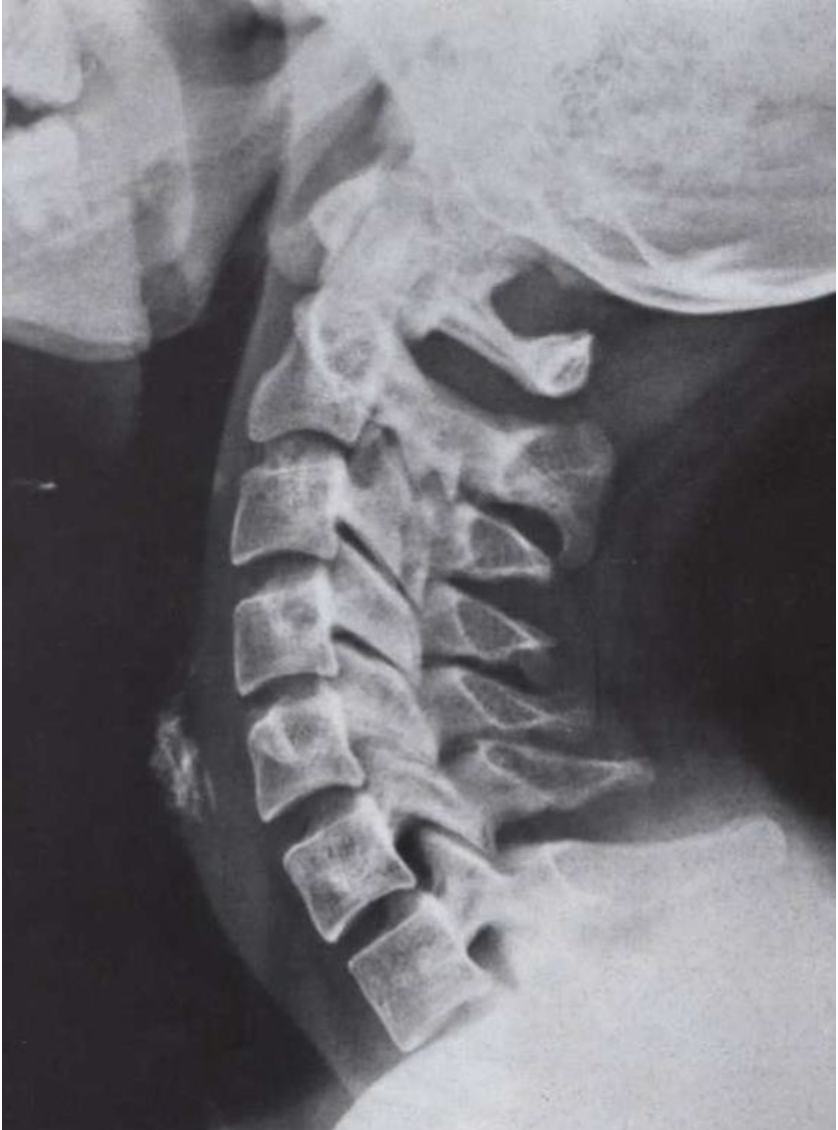

What is this view? What views are missing?

○ Lateral

MISSING

○ APOM

○ AP Lower Cervical

○ Lateral from the other side

○ Right and Left Oblique Posterior)

Davis Series ○ Flexion and extension lateral (along with all other films)